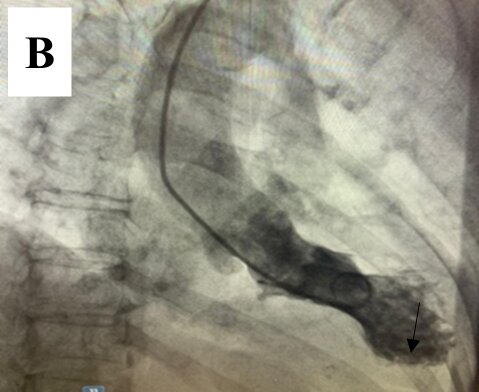

Left ventriculography demonstrated a normal-sized left ventricle with apical akinesis and basal hyperkinesis, resulting in the characteristic "apical ballooning" pattern seen in Takotsubo syndrome (TTS). An apical thrombus was also identified (Figure 4(a) and (b)).

Figure 4. Left ventriculography demonstrating apical akinesis and basal hyperkinesis, consistent with Takotsubo cardiomyopathy. An apical thrombus is clearly identified at the left ventricular apex (black arrow) in both diastole and systole views. (A) End-diastolic frame; (B) end-systolic frame.